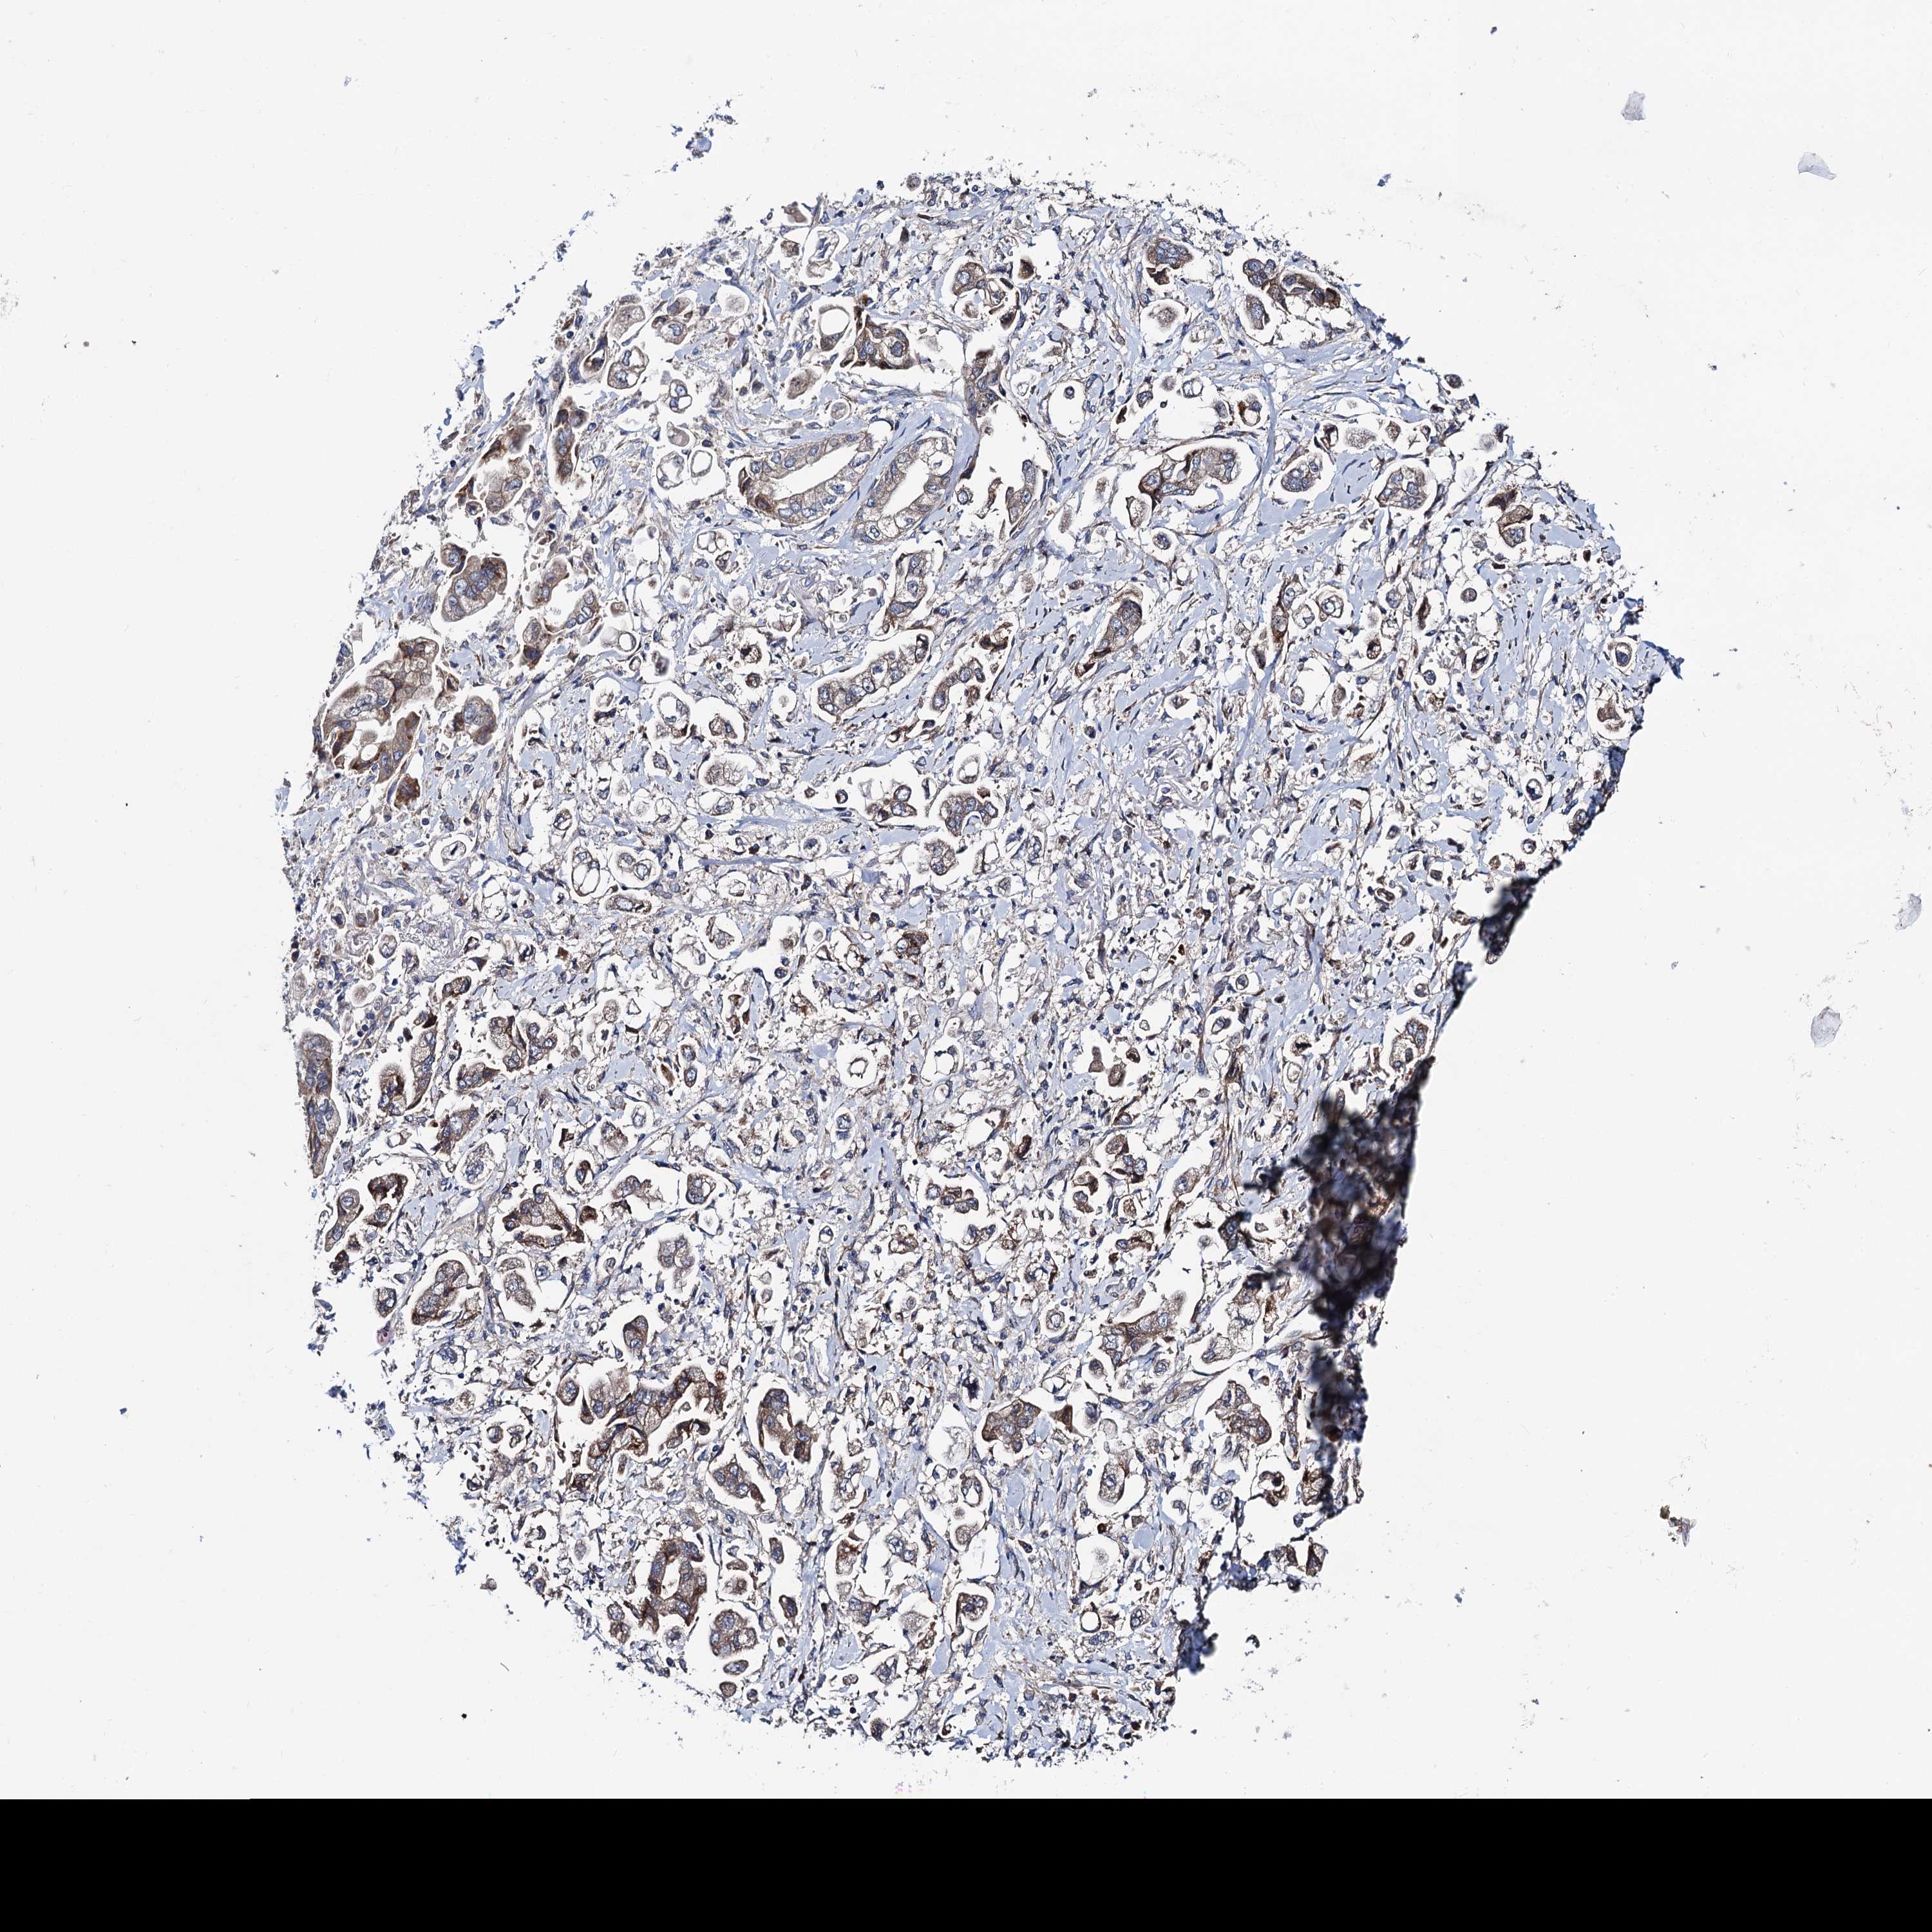

STOMACH CANCER - Protein expressioni

A mouse-over function shows sample information and annotation data. Click on an image to view it in a full screen mode. Samples can be filtered based on level of antibody staining by selecting one or several of the following categories: high, medium, low and not detected. The assay and annotation is described here.

Antibody stainingi

Antibody staining in the annotated cell types in the current human tissue is reported as not detected, low, medium, or high, based on conventional immunohistochemistry profiling in selected tissues. This score is based on the combination of the staining intensity and fraction of stained cells.

Each image is clickable and will lead to virtual microscopy that enables deeper exploration of all samples and also displays staining intensity scores, fraction scores and subcellular localization as well as patient and tissue information for each sample.

Antibody HPA039901

Antibody HPA040006

Staining

High

Medium

Low

Not detected

Intensity

Strong

Moderate

Weak

Negative

Quantity

>75%

75%-25%

<25%

None

Location

Nuclear

Cytoplasmic/membranous

Cytoplasmic/membranous,nuclear

Adenocarcinoma, NOS

Adenocarcinoma, High grade